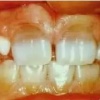

Tetratsükliini liigtarbimise tõttu värvunud hambad

– Hammaste krooni kaltsifitseerumise häired, emaili hüpoplaasiad, on üsna sagedased. Need on nähtavad vahelduvate värvi- ja ehituse muutustena hamba pinnal.

– Hüpoplaasia on tingitud emaili tootvate rakkude normaalse talitluse häirumisest, mida tavaliselt

põhjustavad välised tegurid (näit. nakkused).